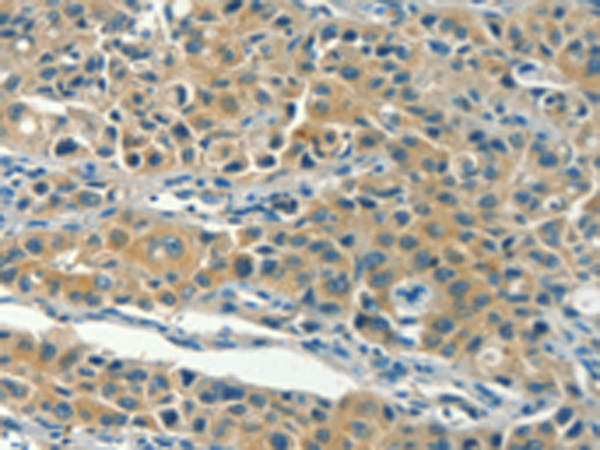

分类: 科研抗体货号: P08010别名: ZFYVE11; FYVE-DSP2应用: IHC反应种属: Human, Mouse